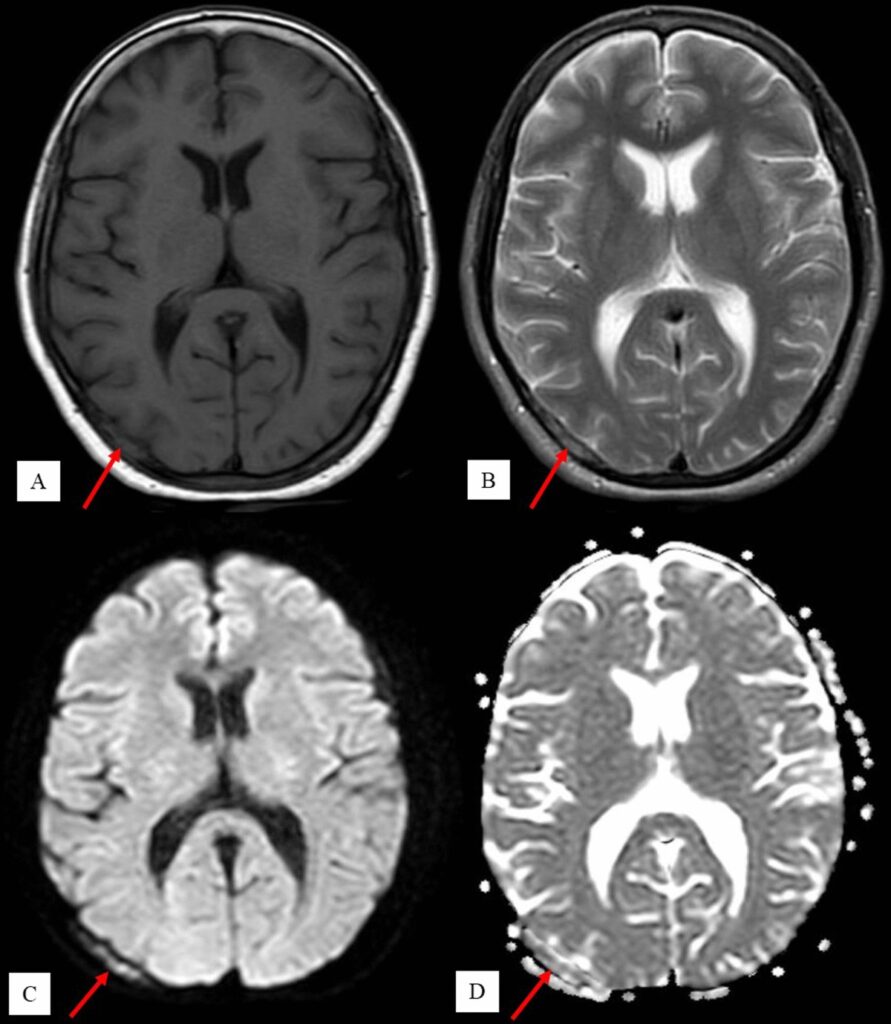

In acute trauma situations, CT scans deliver rapid results crucial for immediate medical decisions. Head injuries require quick evaluation for bleeding, skull fractures, and brain swelling – all clearly visible on CT within minutes.

Which scan is more accurate for diagnosing strokes?

CT quickly identifies bleeding strokes, while MRI better detects ischemic strokes. Emergency protocols often start with CT for speed.

Despite its advantages, CT scanning cannot match MRI’s soft tissue contrast resolution. Brain and spinal cord imaging often requires MRI for detailed evaluation. Cartilage, ligaments, and tendons appear more clearly on MRI examinations.

No. While CT excels at certain tumor types, MRI provides superior soft tissue contrast for brain tumors, spinal cord lesions, and many abdominal masses.